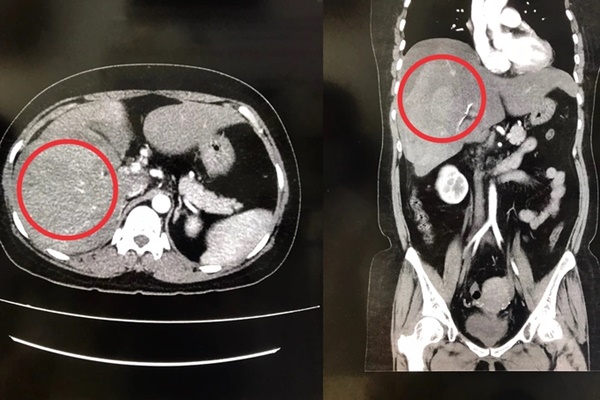

Ảnh chụp CT-scan cho thấy gan phải của chị L. bị vỡ (Ảnh: BV cung cấp).

Đến rạng sáng 20/2, chị L. bất ngờ bị đau bụng dữ dội nên được người nhà đưa đến bệnh viện để điều trị. Qua thăm khám, bác sĩ chẩn đoán chị L. bị dập vỡ gan phải hạ phân thùy V, chảy máu ổ bụng, gây xuất huyết nội rất nguy hiểm.

Hình ảnh chụp gan bệnh nhân trước khi điều trị...